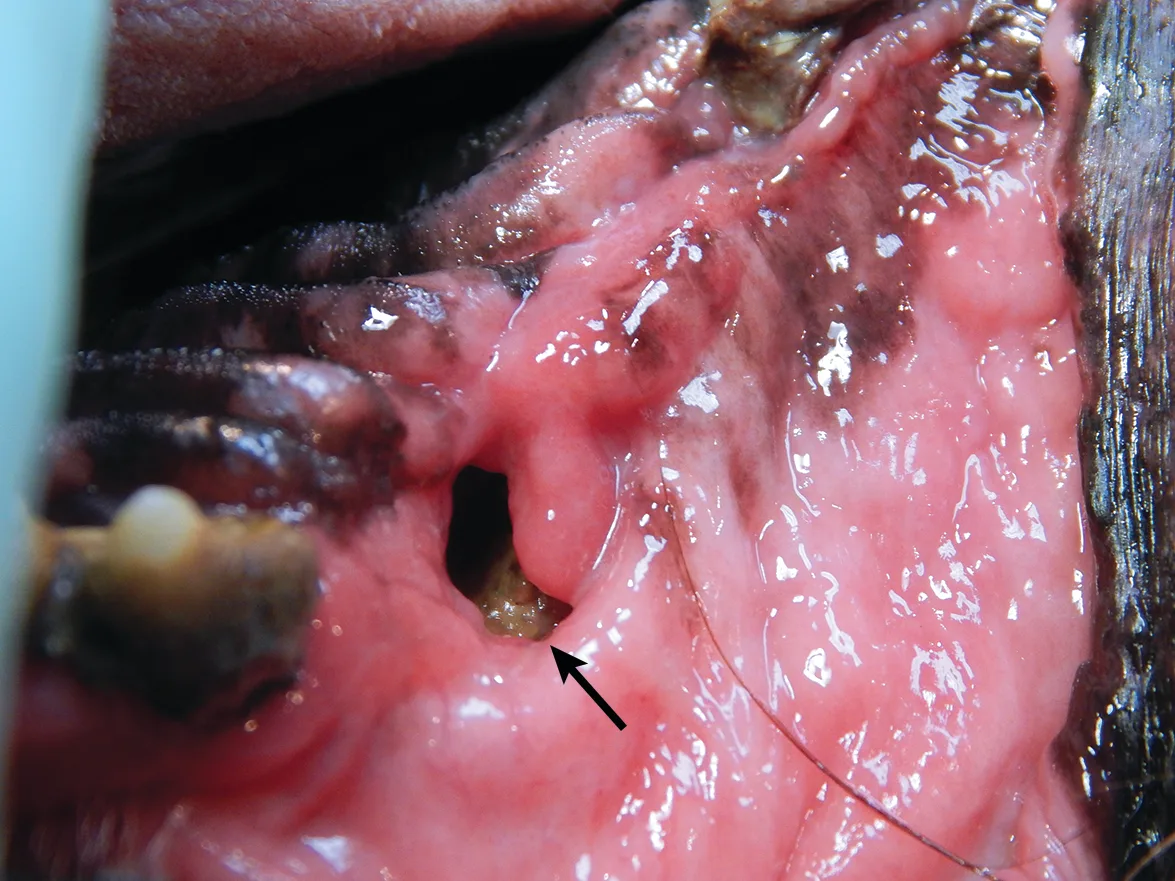

Oronasal fistulas may often be present prior to surgical extraction of maxillary teeth (Figures 6 and 7) but can also be a result of the surgical procedure. Although any maxillary tooth extraction can result in an oronasal fistula, it is most common following extraction of a maxillary canine tooth. Inadequate healing may lead to chronic oronasal fistulation (Figure 8). The quality of the tissue used to close the fistula and lack of wound tension are especially important in closure of oronasal fistulas. Development of a healthy recipient bed for the flap (Figure 9) and use of an Elizabethan collar to prevent self-trauma by the patient can also reduce flap failure.4

A dental probe used to demonstrate the presence of an oronasal fistula (arrow) affecting the right maxillary canine tooth

Appearance of the oronasal fistula in Figure 6 after surgical extraction of the right maxillary canine tooth. Purulent exudate (arrow) is visible in the nasal cavity through the oronasal fistula.